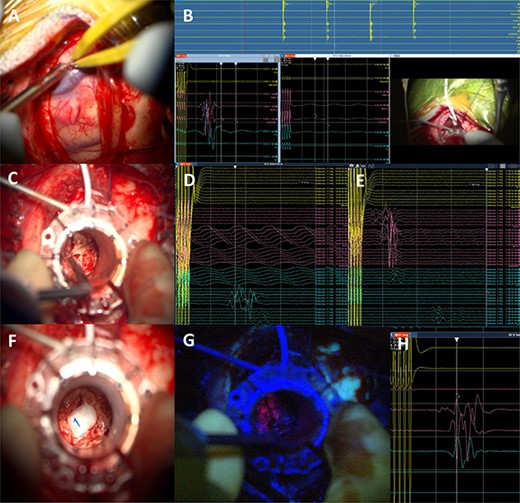

Intraoperative technical illustration: (A) transsulcal approach; (B) subdural strip of electrodes placed under preoperative nTMS and DTI guidance with stable responses at 7 mA; (C) docking of the BrainPath tubular retractor with positive responses of the anterior tibialis at 17 mA during the cannulation of the brain, insertion stopped at this point; (D) stimulation through the tube identified motor responses at 17 mA from lower limb muscles (tibialis anterior and abductor hallucis); (E) direct subcortical stimulation identified motor responses from upper and lower limb muscles at 7 mA; (F and G) Tumour subtotal resection stopped at 5 mA for the upper limb and 7 mA for the whole CST. The tumour demonstrated 5-ALA-induced fluorescence under the BLUE 400 filter; (H) activity from hand muscles at 5 mA threshold during removal of BrainPath tubular retractor before closure.

Once the superficial aspect of the lesion was reached, positive stimulation of the lower limb was identified at 17 mA (Fig. 4). The tubular retractor was fixed with a Leyla retractor system and held manually to prevent displacement. Multiple tissue samples were obtained from 5-ALA-induced fluorescent tissue. Intraoperative smear was consistent with high-grade lesion. After the biopsy was performed the tubular retractor was slowly removed. Using a monopolar probe for subcortical stimulation directly through the surgical site, we were able to confirm the proximity to the CST at 5 mA to the lower limb motor fibres. Cortical MEPs were stable during the whole procedure.

5-Aminolevulinic Acid (5-ALA) was given orally 2 h before the surgery. The least disruptive trajectory was selected taking into account the previous biopsy and the preoperative mapping information (Fig. 3). Under Stealth guidance, a skin incision was made overlying the planned craniotomy site. After the craniotomy, the dura was opened and a subdural strip of electrodes was placed over the primary motor cortex. Replicable motor responses from the hand muscles were obtained at 7 mA current intensity (Fig. 4). Motor evoked potentials (MEPs) were obtained continuously throughout the procedure. A transsulcal parafascicular approach was used. The sulcus was opened sharply under the microscope. At the depth of the sulcus, a preselected tubular retractor (NICO BrainPath 75 mm × 13 mm) was passed to the superficial surface of the lesion. While performing brain cannulation to the lesion, a monopolar probe (INOMED©) navigated with SureTrack (MEDTRONIC©) was used to perform continuous subcortical stimulation, train-of-five technique using high-frequency stimulation.